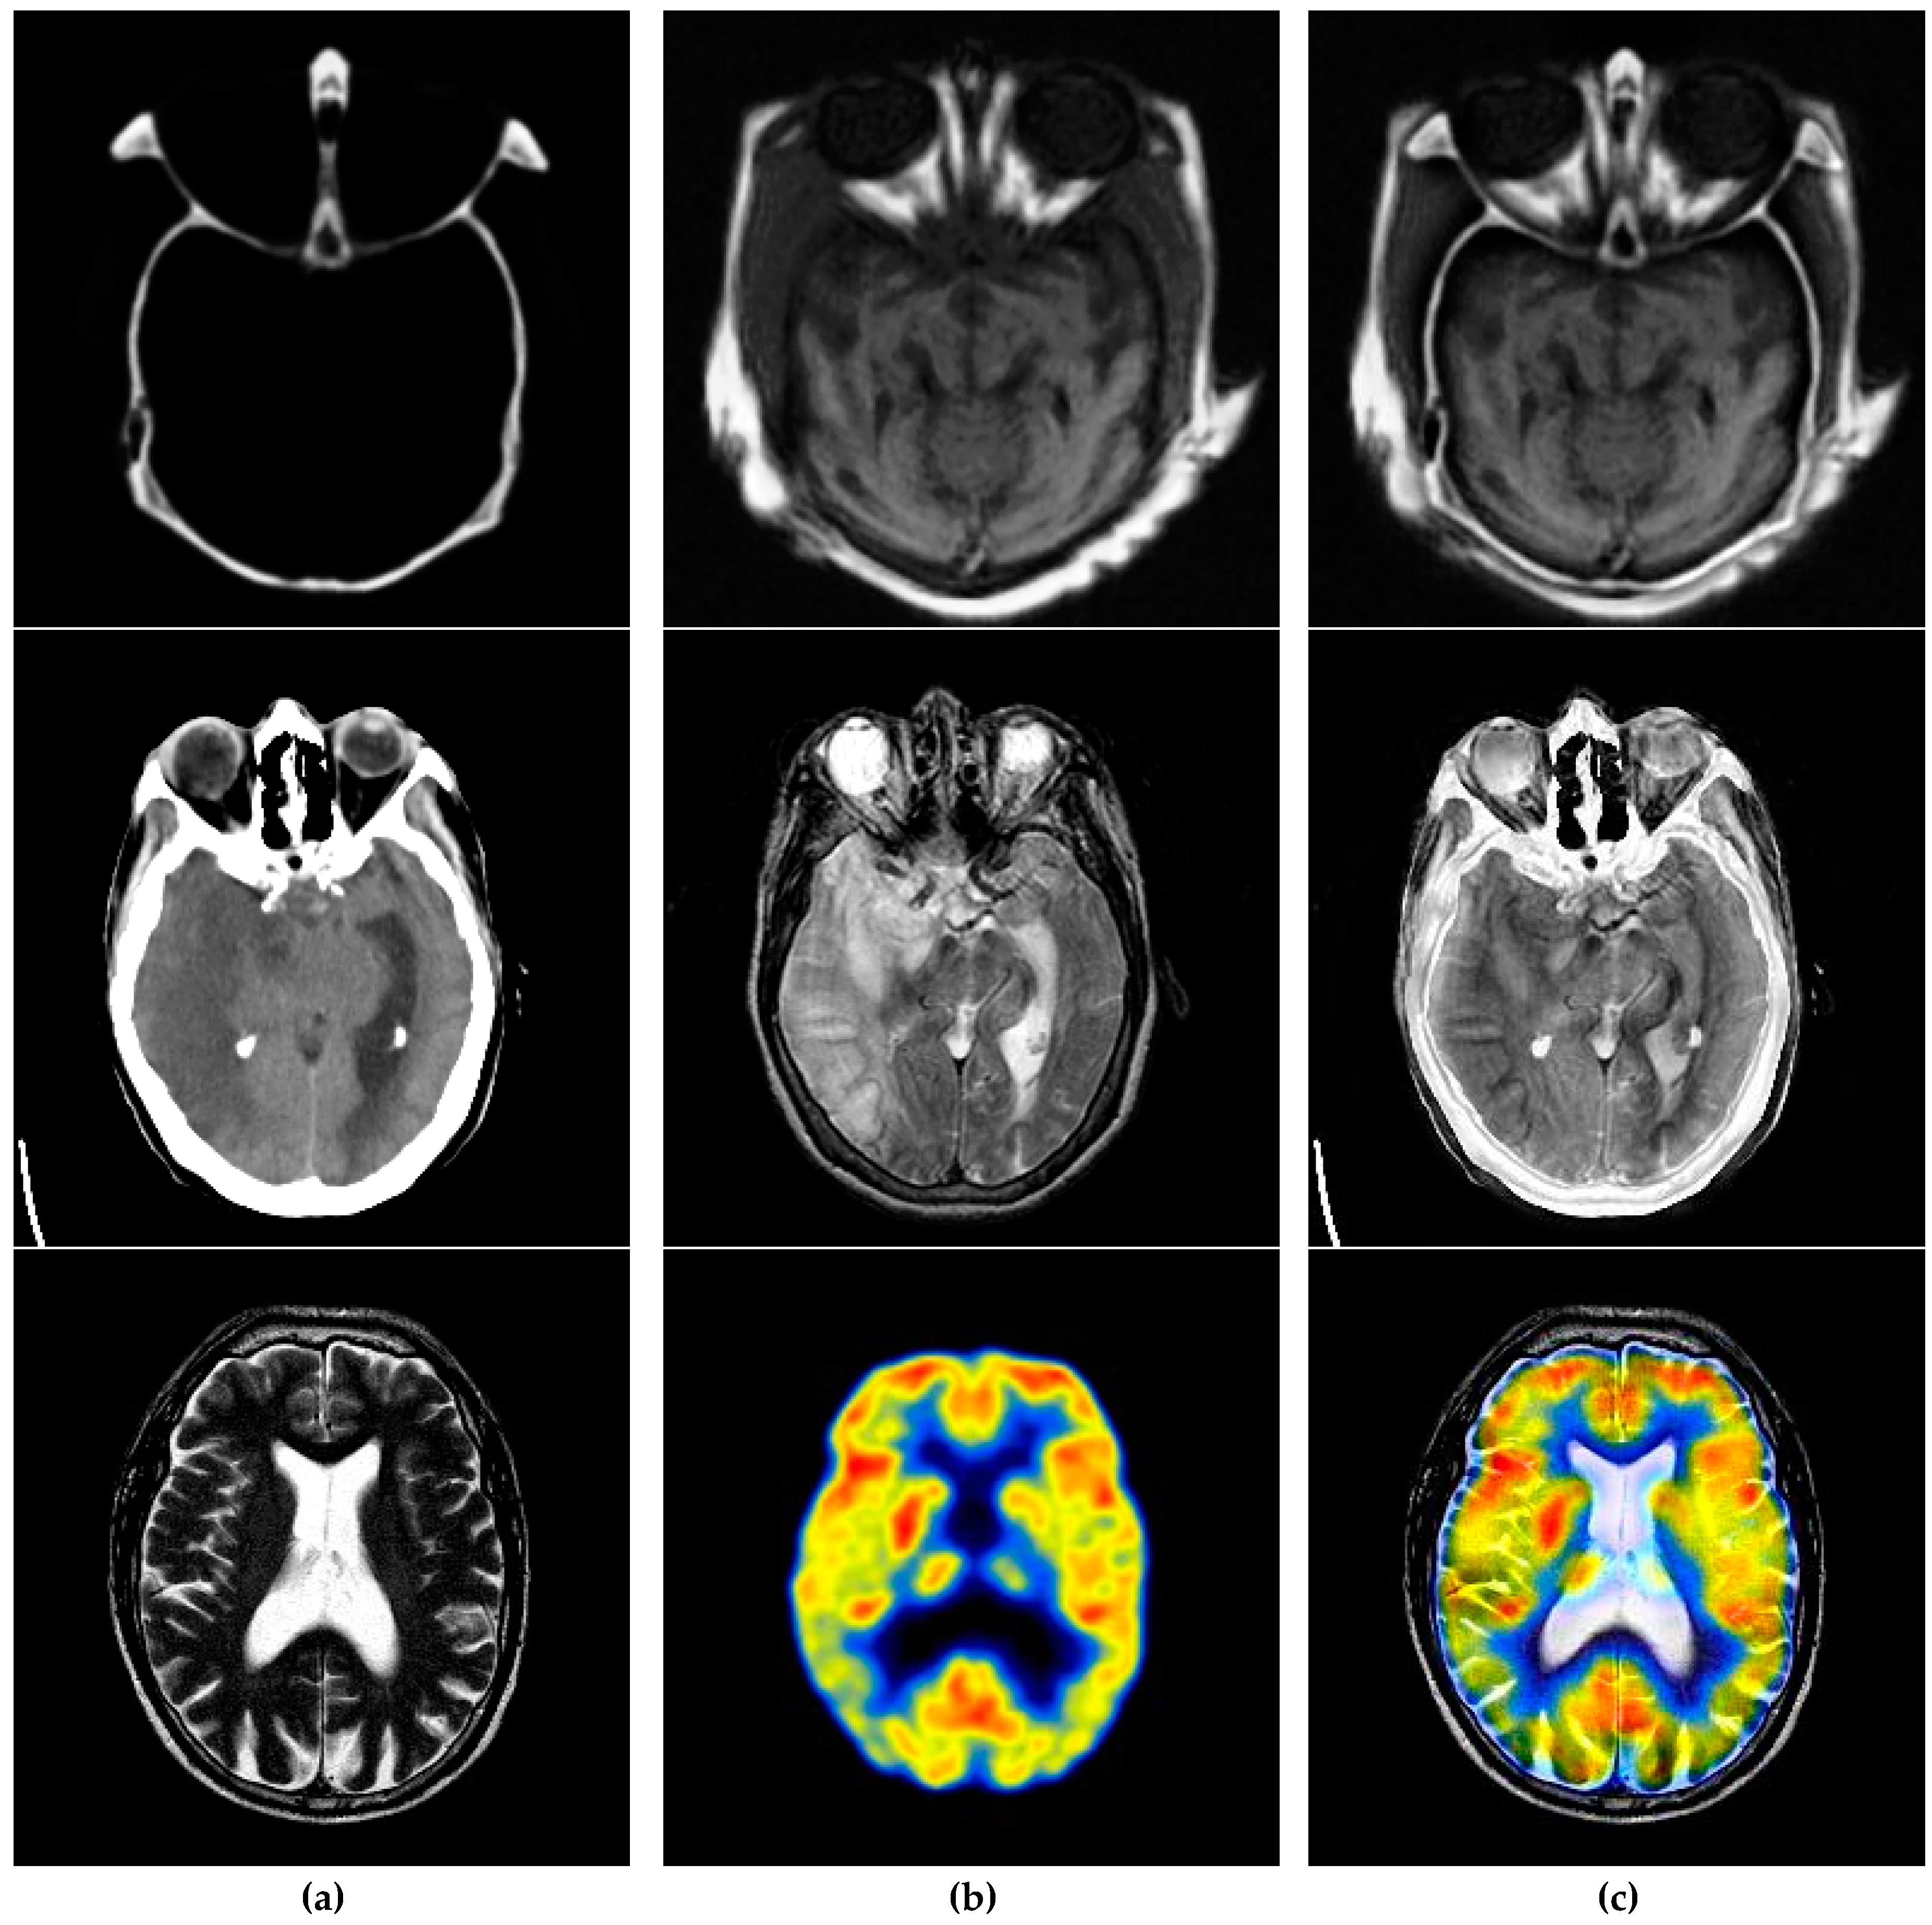

6.3. Application Extension